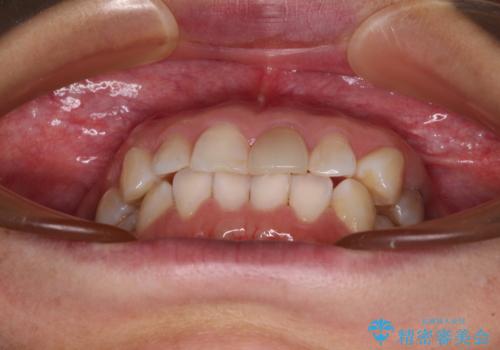

- 上下前歯のデコボコを気にして来院された患者様です。

カウンセリングにて詳しく話を聞いたところ、一番気になっているのは下顎前歯の叢生であり、上顎犬歯はあまり気になっていないとのことでした。

矯正治療は、歯の後戻りを抑制するために、治療終了後も保定装置をしっかりと使用していただくことが必須であるため、気になっている下顎だけを整えることで、その負担を半減できると考え、下顎のみの部分矯正として治療を行うこととしました。

装置としては、叢生の程度が強くなかったため、インビザラインの廉価版であるモデレート・パッケージを使用することとしました。

当院では治療前の歯列が整っていない限り、下顎前歯の舌側をワイヤーで固定するようにしています。下顎のみの部分矯正としたことで、マウスピース保定の負担を軽減することができました。

上顎は、失活して歯の色が変色しているため、将来的に補綴治療で自然な口元に仕上げていきたいとのことでした。